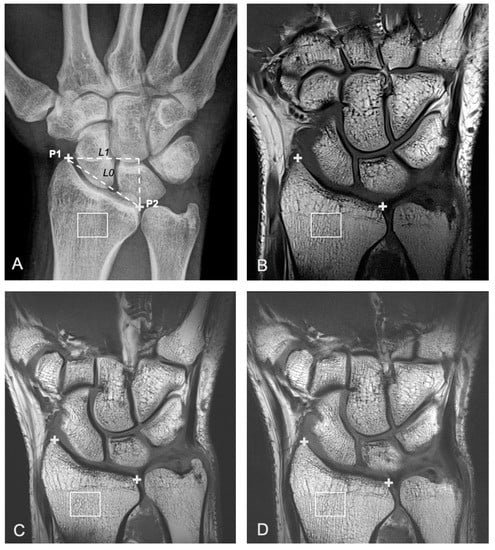

2.2. Radiography

2.3. Magnetic Resonance Imaging

2.4. Bone Texture Analysis